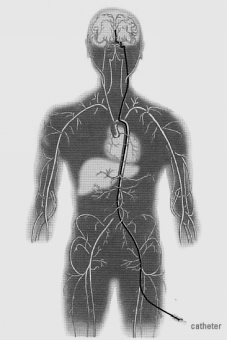

动脉瘤介入栓塞治疗示意图